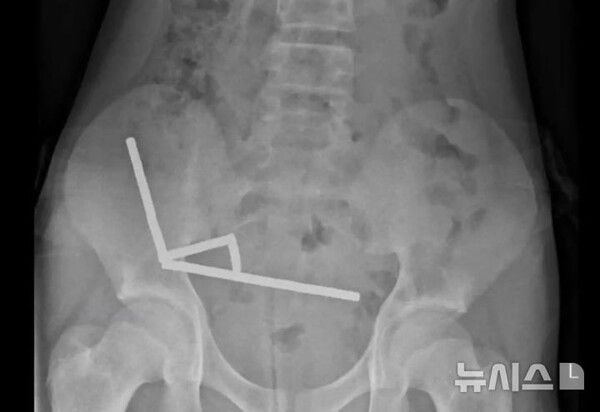

사진 = 뉴시스

의료진은 엑스레이 검사에서 그의 장 속에 약 200개의 작은 네오디뮴 자석이 사슬 형태로 뭉쳐 있는 것을 발견했다.

이 자석들은 서로 강하게 끌어당기며 장 벽을 압박해 혈류를 차단했고, 그 결과 장 점막 일부가 괴사했다. 의료진은 자석과 손상된 장 조직을 함께 제거하는 수술을 진행해 소년의 장에서 5×2㎜ 크기의 자석 200여개를 회수했다.